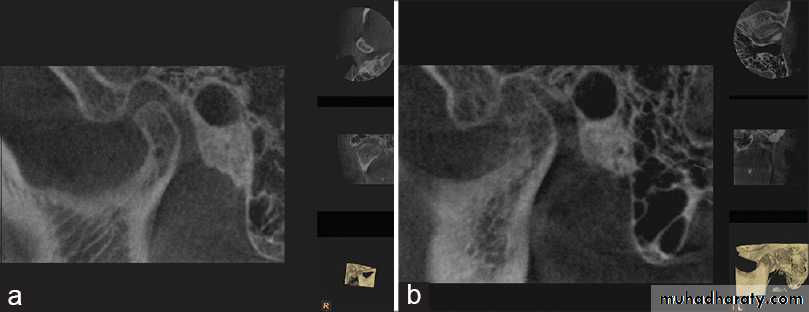

8Radiology

Radiography confirms a clinical diagnosis.The condyle may translate beyond the articular eminence normally, without a dislocation, so clinical information is essential. The condyle will be anterior and superior to the ‘summit’ of the articular eminence.

Dislocation

NB. Normally: the condyle may be translated anterior to the eminence as far as 5 mm.Dr. Mohammed Amjed Alsaegh, 2021